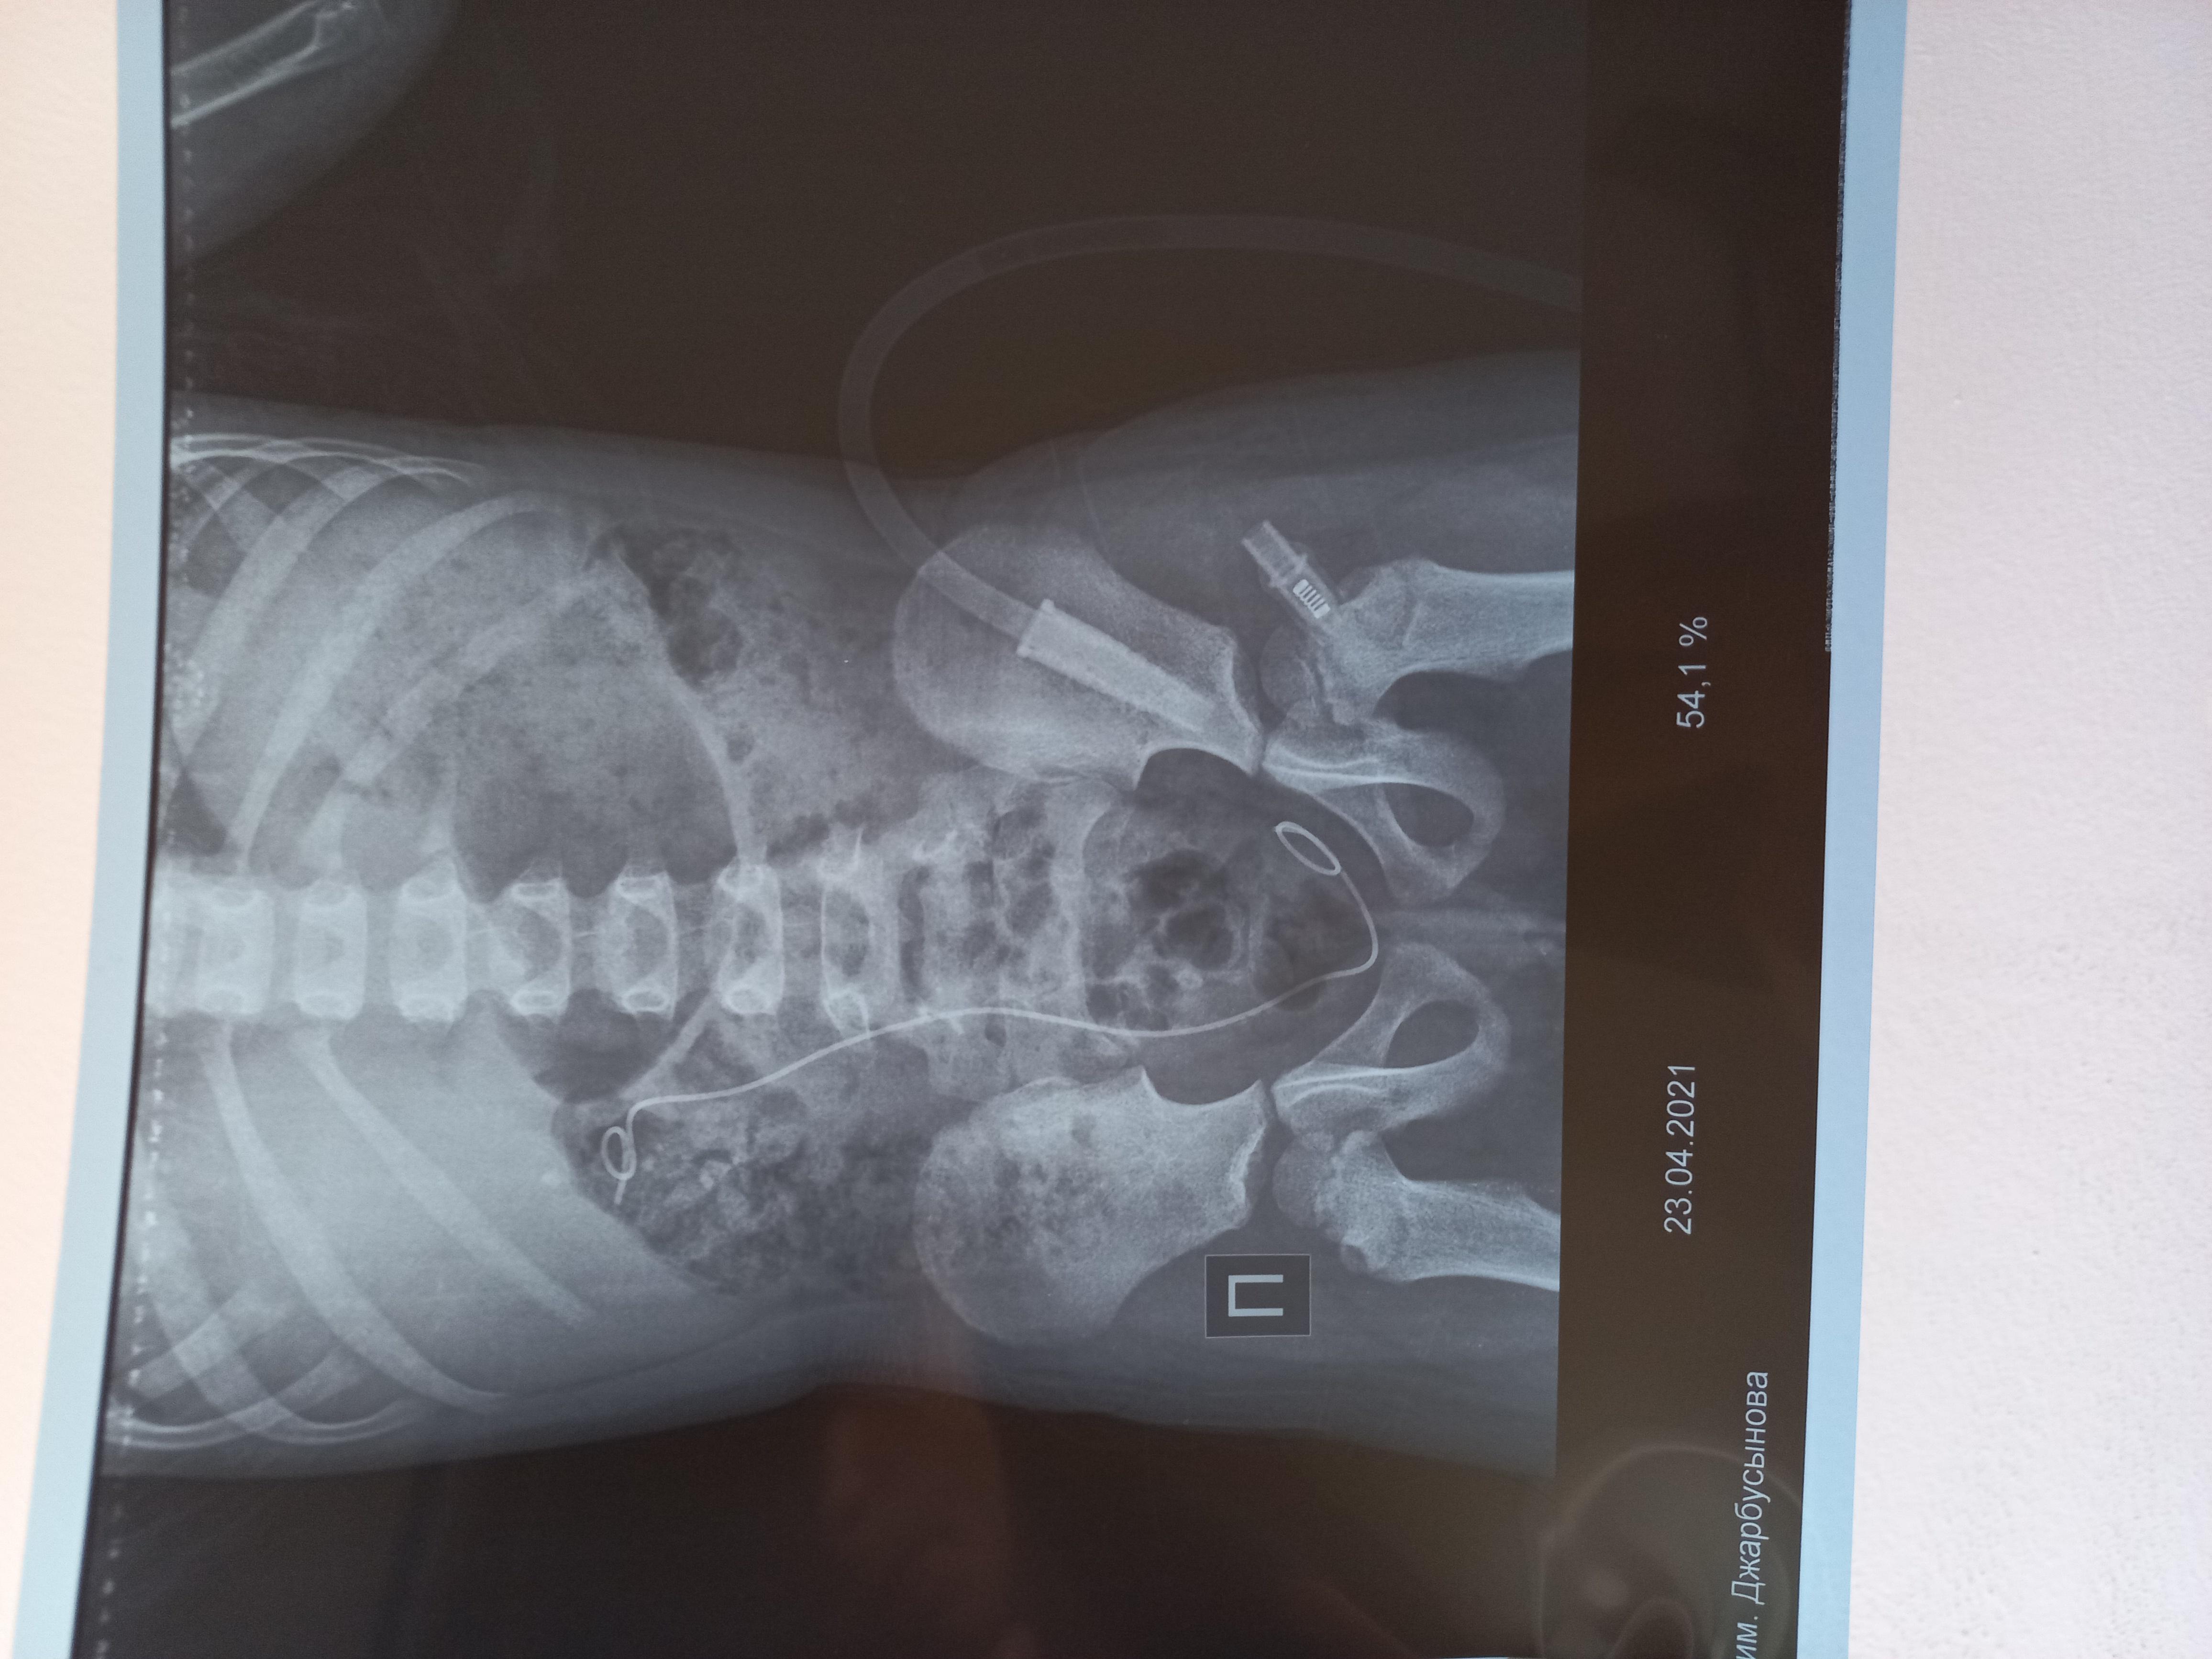

Здравствуйте! У моей дочери(5 лет)в феврале этого года обнаружили камни в почках фосфаты и оксалаты размером 1.6 мм и 0.6 мм, плотностью 1300 и 600 едХ. В марте была произведена операция по дробилению камня-ретроградная литотрепсия с установкой стент-катетора, в апреле трансуретральное устранение обструкции из мочеточника и почечной лоханки с заменой стент-катетора. Через неделю после выписки с больницы выпадает стент-катетор и в результате развивается гидронефроз. В начале мая опять же ставят стент-катетор и опять же он выпадает. В конце мая опять же производят операцию ЭУВЛ без установки стент-катетора. Последние снимки УЗИ показали, что камни ещё присутствуют в лоханке и в нижней чашки 7.6, 5.9, 5.8, 5 2,3.7, 4.9. Как вывести эти камни из почки и как можно выявить причину образований этих камней? Какие лекарства необходимо принимать, чтоб растворить камни?

Здравствуйте! Судя по представленным документам, Вашу дочь лечат высокопрофессиональные доктора и хирурги. При имеющейся ситуации вопрос о "растворении" конкрементов не идёт. Действительно, одномоментно вывести все фрагменты при естественных малых размерах мочевыводящих путей у ребёнка затруднительно. Поэтому приходится прибегать к неоднократным эндоскопическим процедурам, что, однако позволяет избежать более травматичного открытого хирургического вмешательства. Не исключено, что будет предложено очередное эндоскопическое вмешательство. К сожалению, вряд ли возможен вообще неинвазивный метод лечения в данном случае.